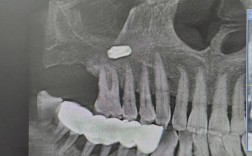

- 医生会评估你的口腔状况,拍摄全景片(曲面断层片)和必要时CBCT(锥形束CT),精确判断智齿的位置(埋伏、水平、垂直、倒置等)、与邻牙及下颌神经管的关系、牙根形态、骨质情况等,制定手术方案。